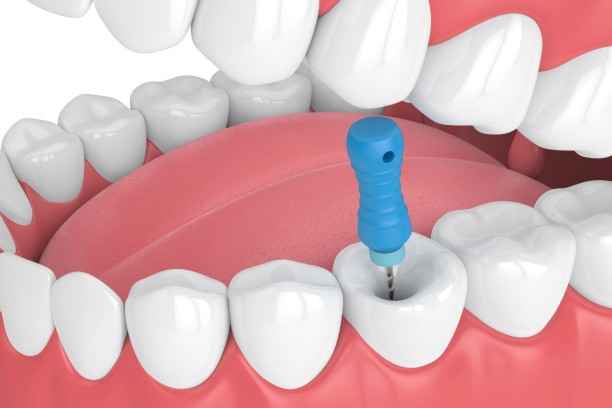

Root Canal Treatment

Saves infected teeth by removing decay and relieving pain.

Endodontic Retreatment

Re-treats previously failed root canals to preserve your natural teeth.